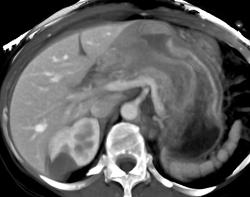

GIST Tumor